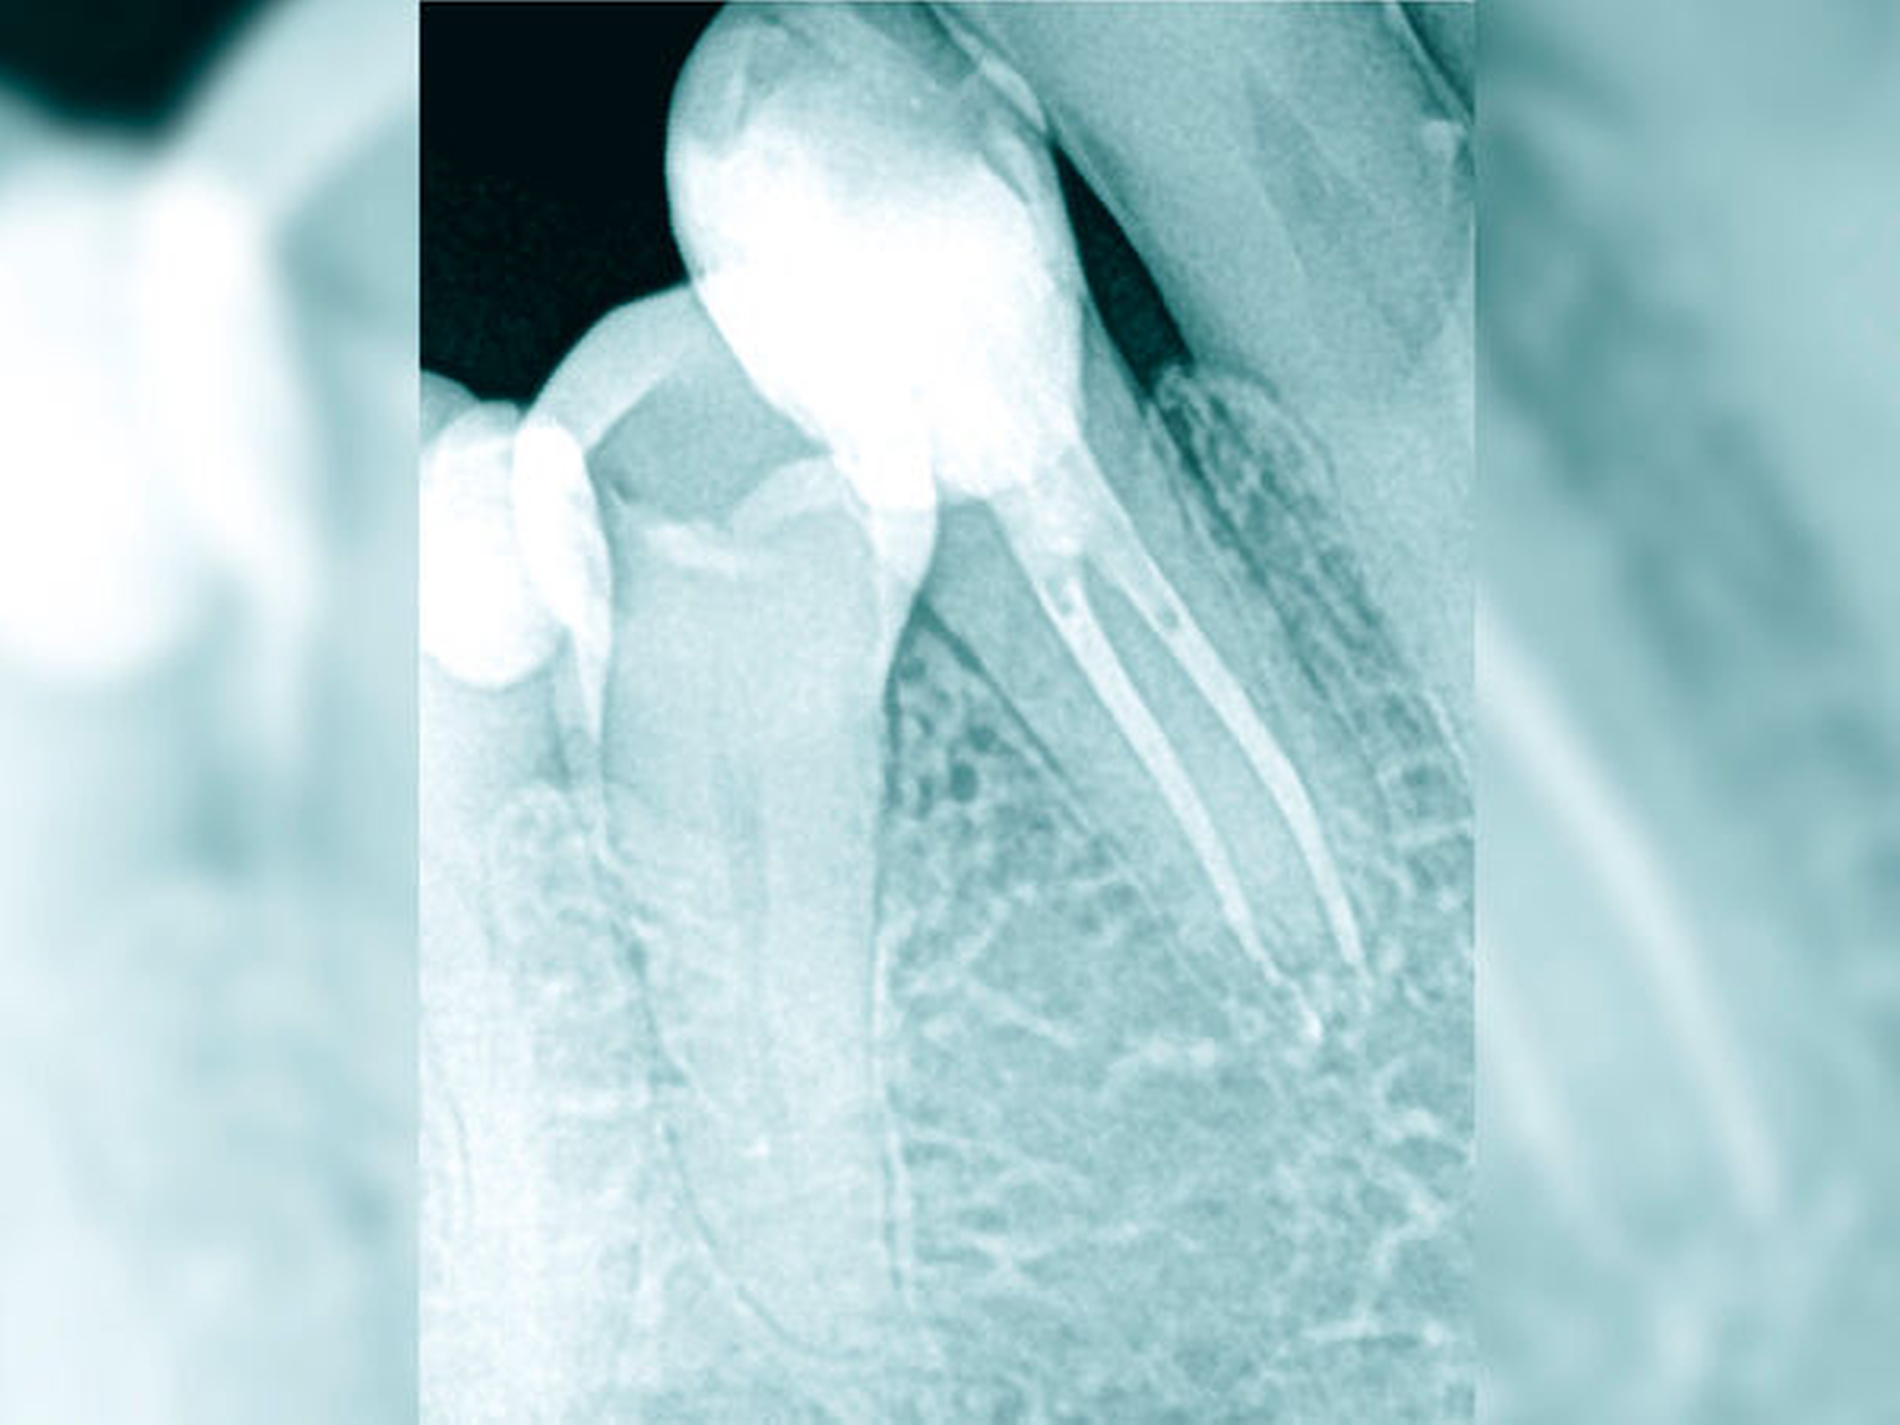

Die Schwierigkeit in der Therapie nimmt zu, wenn die Wurzelkanalkrümmung mehr als 30 Grad beträgt, der Krümmungsradius abnimmt (enge Krümmung) oder Mehrfachkrümmungen vorliegen [Duke et al., 2015; Pedulla et al., 2020]. Typisch für Mehrfachkrümmungen sind vor allem mesiale Wurzelkanäle unterer Molaren (Abbildung 4).

Sollte eine Konfluenz beider mesialer Wurzelkanäle am unteren Molaren vorliegen, kommt es zu einem abrupten Richtungswechsel und Instrumente können leichter frakturieren oder Stufen präparieren, so dass die Arbeitslänge nicht mehr erreicht werden kann.